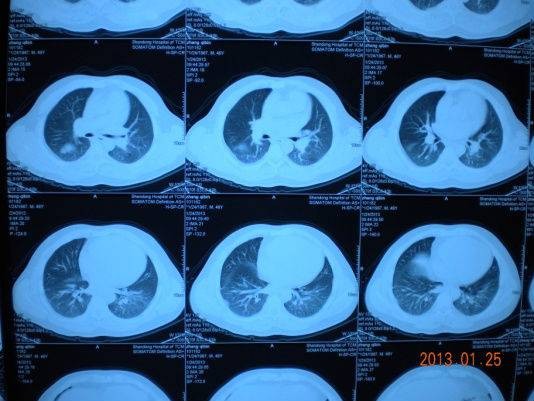

以上方案治疗10天,患者症状明显改善,咳喘明显减轻,复查胸部CT:间质渗出、肺部炎症均明显吸收好转,出院。

治疗后

按:影像学出现肺部间质改变的原因很多,首先要明确病因。本例患者按特发性间质肺炎给予激素、抗生素治疗无效,后予抗结核治疗均无效。而患者心彩超示:肺动脉压高、二尖瓣脱垂,故肺内淤血水肿,易合并炎症。中西医结合治疗,改善心功能,同时配合中药清热化痰,益气活血,抗炎抗感染,减少渗出,降低肺高压。短时间内使病情明显改善。